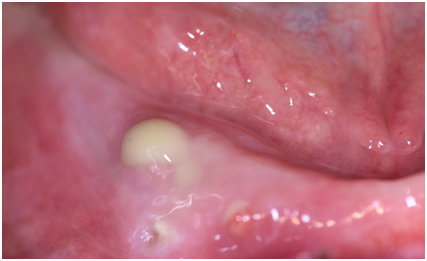

A 84-year-old Caucasian female referred to the Sector of Oral Medicine “V. Margiotta”, University Policlinic “P. Giaccone” of Palermo complaining of acute pain of one month’s duration on the gingiva, to the right side of the mandible. The patient had a history of osteoporosis on treatment with per os alendronate for 15 years. She also had a history of hypertension treated with calcium channel blocker. On clinical examination there was a mucosal fistula with purulent discharge (Figure 1) and a chronic ulcerative lesion (Figure 2) on the left border of the tongue. The patient was edentulous, wearing two incongruous total dentures; she did not report any teeth extractions in the previous 8 years. After obtaining an informed consent from the patient, an incisional biopsy was performed on the left border of tongue and a panoramic x-ray and maxillary computer tomography scan (CT) was also prescribed. Histopathology confirmed a diagnosis of OSCC in the non-smoker and non-drinker patient; on the other hand, panoramic x-ray and CT showed the presence of the sclerosis bone with a radio-transparent edge in lower right mandibular hemi-arch. Both clinical and radiological features were confirmed BRONJ, stage IIb (according with SICMF/SIPMO classification).8 She was treated with antibiotics and chlorhexidine mouth rinse, and referred to III level plastic surgery Sector for staging and treatment of OSCC and BRONJ.

Figure 1 Mucosal fistula with purulent discharge.

Figure 2 Chronic ulcerative lesions on the left border of tongue.